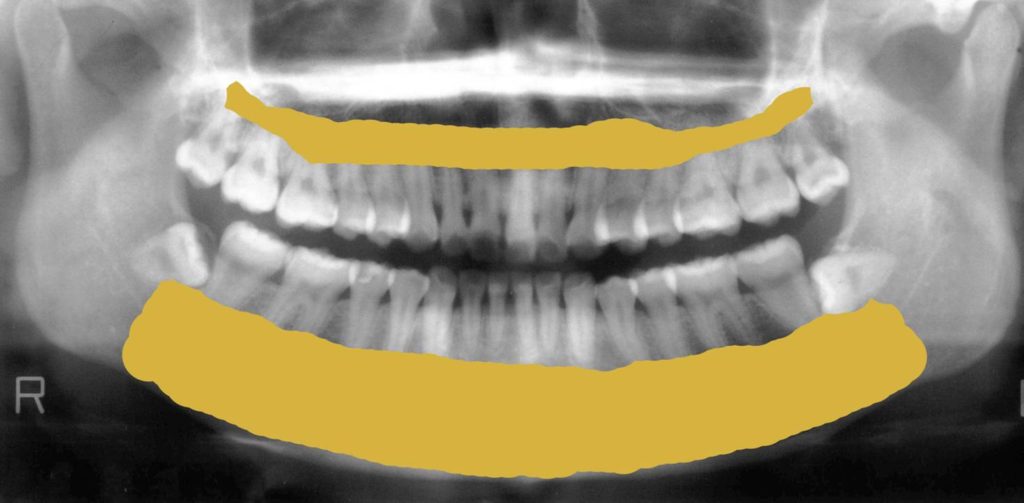

次の写真は歯科レントゲンで見る下顎の骨です。

赤く線を引いている部分が下の顎の骨部分になります。

硬い部分が白くうつります。

硬い部分とは骨です。

歯科レントゲンで見る上顎(あご)の骨

次に上の顎の骨をみていきましょう。

青い線の上側が上の顎の骨部分になります。

下図のように骨がしっかりある方もいらっしゃいます。元々はみなさん骨があったはずです。

歯周病やなんらかの理由で次の図のように歯が溶けて少なくなっている方もいらっしゃいます。

歯を支えている骨部分がもともとはこれだけの量があります。

しかし骨が少なくなるとこんな風になってしまうのです。